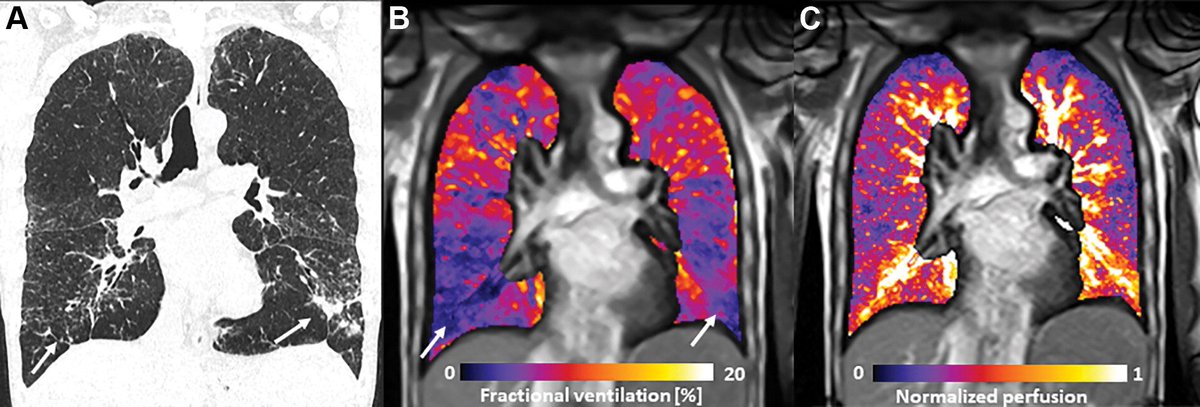

We are happy to present our preliminary work showing the potential of low-field MRI for morphologic and functional lung imaging #lowfield #MRI #Basel pubs.rsna.org/doi/10.1148/ra…

We are happy to present our preliminary work showing the potential of low-field MRI for morphologic and functional lung imaging

What can functional MRI reveal about changes in lung perfusion after vaping and cigarette smoking? Dr. Kligerman reviews the article by Nyilas and Bauman et al in this editorial. bit.ly/3DJFyMq

MRI shows promise as a noninvasive way to assess the short-term effects of vaping and tobacco smoking -- effects that manifest in different ways on medical images, says a new study in Radiology. #radiology #MRI bit.ly/37pGYiP